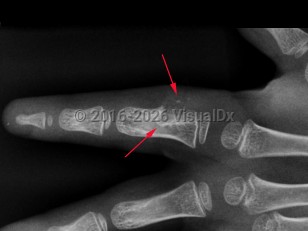

Imaging Studies image of Periosteal chondroma - imageId=8364755. Click to open in gallery.  caption: '<span>Radiograph of the ring finger demonstrates a lytic lesion involving the ulnar aspect of the proximal phalanx with saucerization of the cortex, a deep sclerotic margin, and chondroid calcifications extending into the soft tissues. These imaging findings at this location are most suggestive of a juxticortical chondroma.</span>'

Radiograph of the ring finger demonstrates a lytic lesion involving the ulnar aspect of the proximal phalanx with saucerization of the cortex, a deep sclerotic margin, and chondroid calcifications extending into the soft tissues. These imaging findings at this location are most suggestive of a juxticortical chondroma.